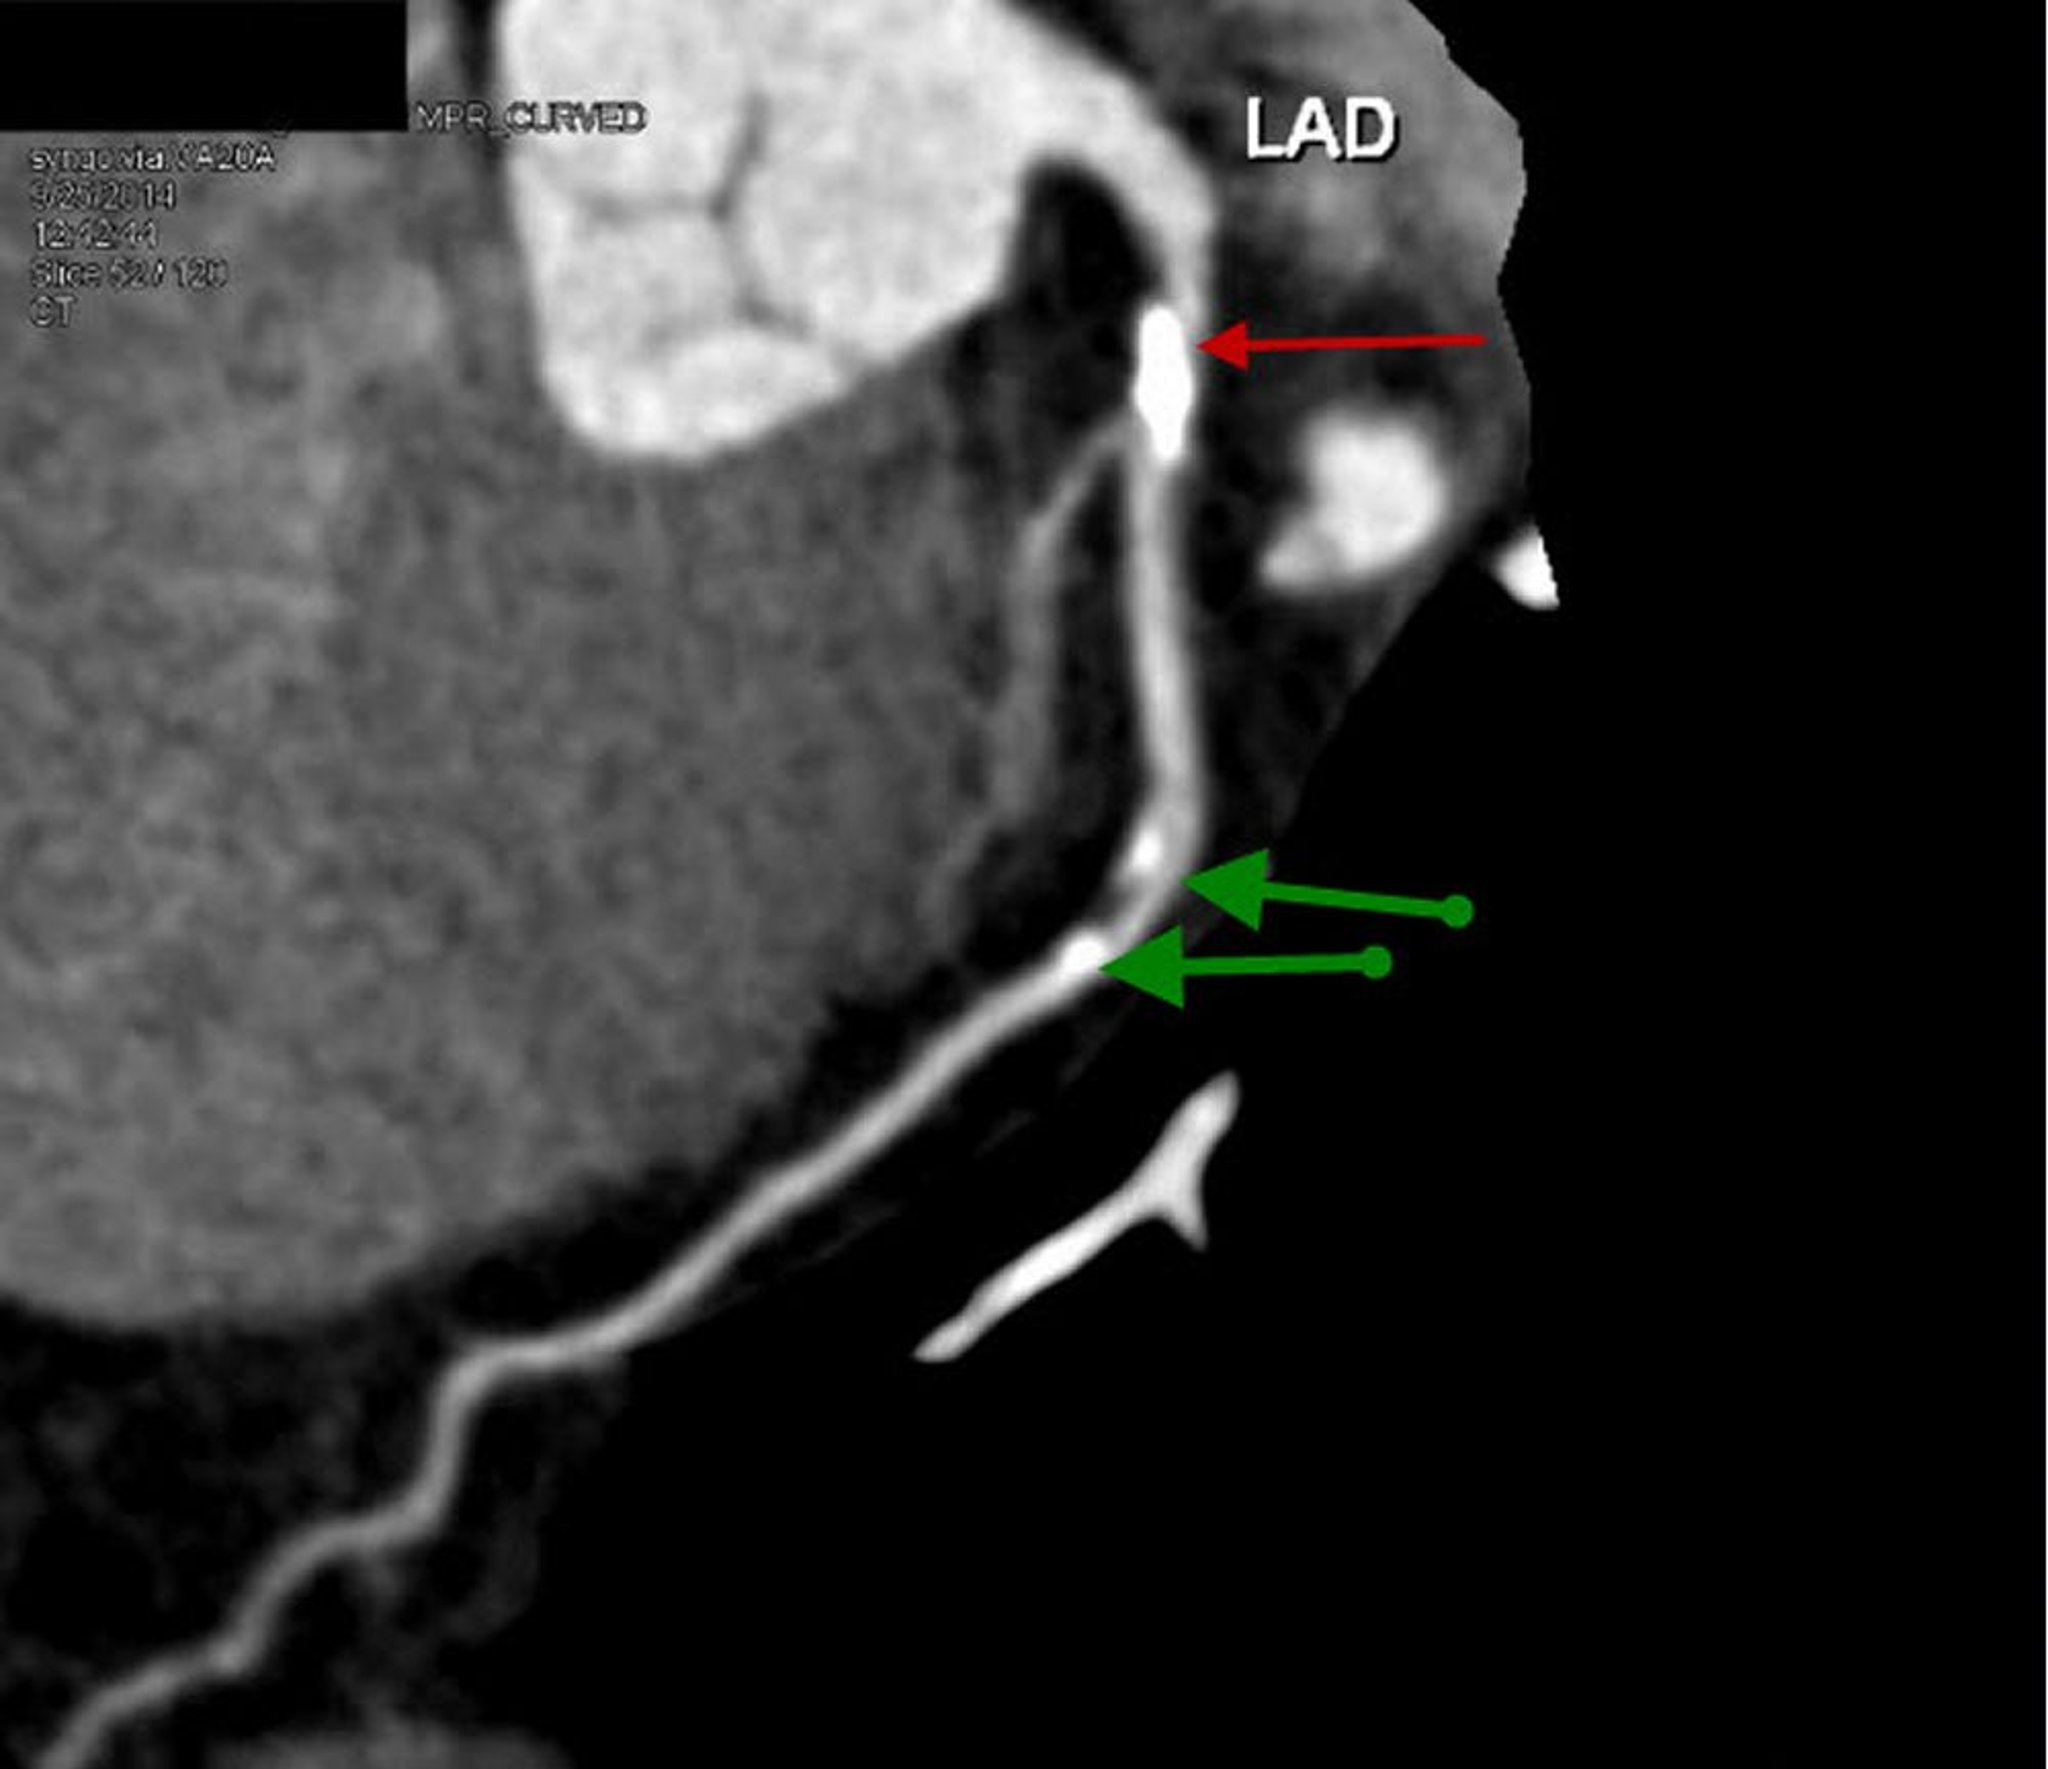

КТ с контрастированием, показывающая коронарную недостаточность

КТ с контрастным веществом демонстрирует реконструированный сагиттальный вид проксимальной части левой передней нисходящей артерии с выраженными кальцифицированными бляшками и 70-процентным стенозом (красная стрелка). Средний LAD показывает умеренный стеноз 20–30% (зеленые стрелки).